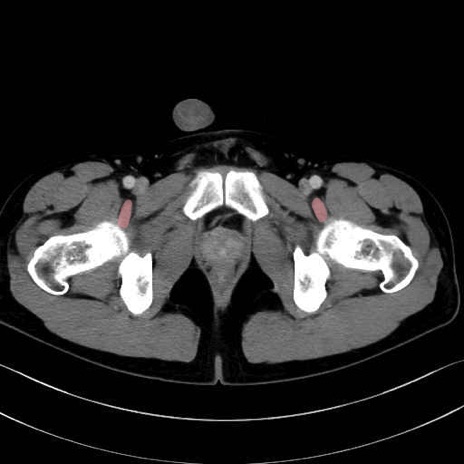

4. 深層外旋六筋(股関節の深部)

内閉鎖筋 (Obturator internus)

外閉鎖筋 (Obturator externus)

大腿方形筋 (Quadratus femoris)